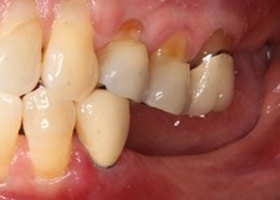

假牙完成照

因植牙恢復正常咬合